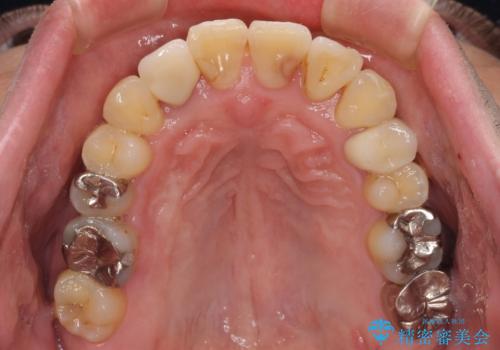

矯正治療でインプラント埋入を行い、矯正治療後に気になる前歯と合わせてオールセラミッククラウンによる補綴治療を行うこととしました。

骨造成や歯肉移植など、治癒期間の長い処置を必要としたため治療期間は長くなりましたが、安定した咬み合わせと整った歯列となり、患者様には大変満足していただきました。